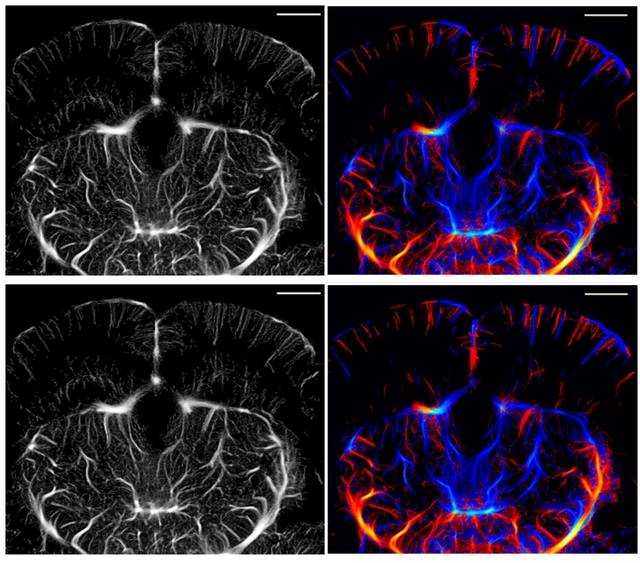

국내 연구진이 기존 초음파 장비를 활용해 적은 데이터 신호만으로 뇌 속 미세혈관까지 고해상도로 볼 수 있는 영상기술을 개발했다.

대구경북과학기술원(DGIST)는 유재석 로봇및기계전자공학과 교수와 현정호 뇌과학과 교수 연구팀이 초음파 기반 초해상 영상 기술인 ‘초음파 국소화 현미경’(ULM)의 효율성을 크게 높인 ‘ULM-Lite’를 개발했다고 18일 밝혔다.

ULM은 혈액 속에 있는 초음파 조영제(마이크로버블)를 따라가며, 그 움직임을 일일이 추적해 미세혈관의 구조를 초고해상도로 재구성해 기존 초음파로 전혀 볼 수 없던 머리카락 굵기의 수십 분의 1 수준의 혈관 지도를 그릴 수 있다.

연구팀은 기존 초음파 장비를 그대로 쓰면서 초음파 신호 중 핵심 정보만 남기고 불필요한 데이터를 과감히 줄이는 새로운 분석 방식을 고안했다. 이를 통해 초음파 신호의 유효 대역폭을 약 67% 줄이고, 혈관 구조에 꼭 필요한 정보만으로 효율적으로 추출하도록 설계했다.

그 결과, 데이터 용량을 기존 대비 3분의 1 수준으로 줄였고, 영상의 선명도는 기존과 동일했다. 영상 처리 속도도 30% 가량 빨라졌고, 수술이나 형광물질 없이 비침습적으로 뇌 전체를 선명하게 볼 수 있다.